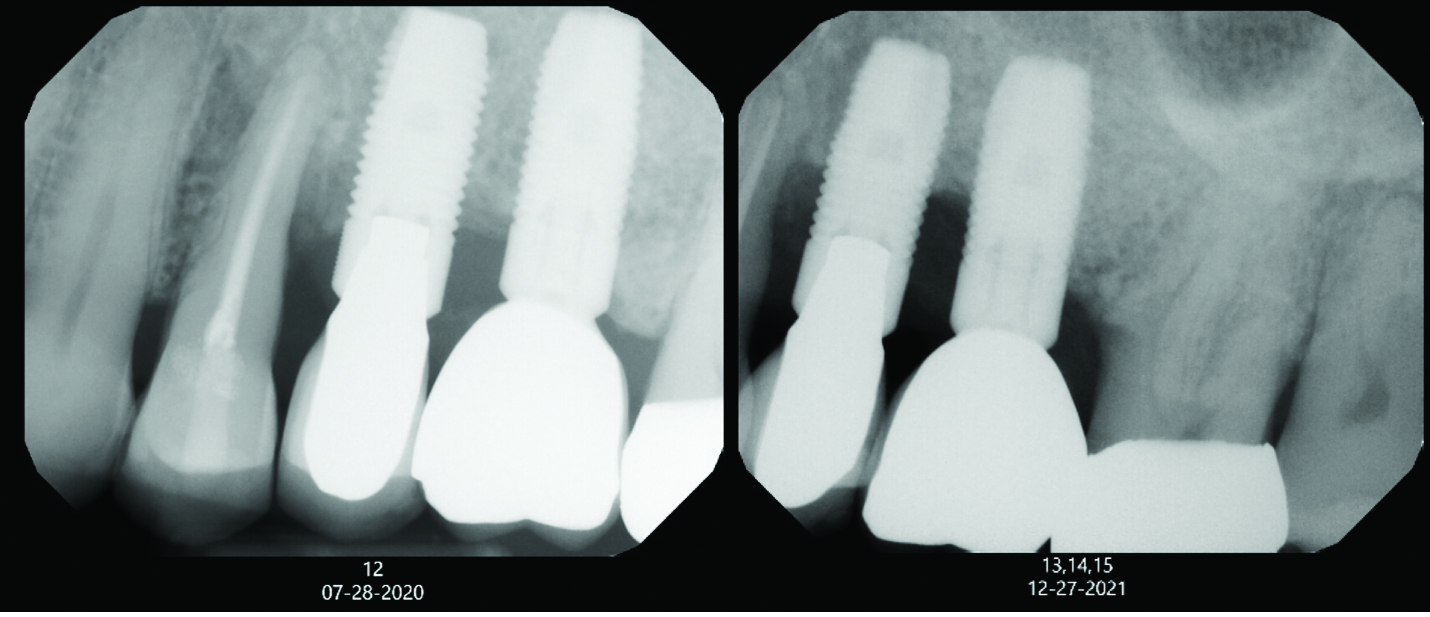

Fig 1. A patient radiograph from July 2020 is seen on the left. Just 1.5 years later, in December 2021, the patient presented with significant bone loss at implant sites Nos. 13 and 14, as seen on the right. The patient had become an uncontrolled diabetic during this time. This case emphasizes how changes in medical history, such as developing diabetes, can affect the peri-implant supporting structures.

Figure 1

A degree of personalization is involved in implant maintenance therapy beginning with an evaluation of the patient's motivation and ability to maintain good oral hygiene prior to implant placement.27 Patient compliance is essential, and inadequate oral hygiene may be a contraindication to implant placement.10 Research shows that plaque buildup surrounding implants might exacerbate mucositis lesions after only 3 months of plaque accumulation.28 Therefore, similar to periodontal maintenance, peri-implant maintenance should be performed every 3 months.9,28 Clinical parameters for monitoring dental implants include probing depth, presence of bleeding on probing (BOP), suppuration, mucosal redness, plaque, keratinized mucosa, occlusion/prosthetic stability, and vestibular depth.10,11 Maintenance visits should also include radiographic evaluation if necessary, a review of the patient's medical history, and demonstration/evaluation of the patient's oral hygiene habits.9,10 Any changes in medical history, such as the onset of diabetes, and/or ability to maintain oral hygiene may affect the patient's susceptibility to peri-implantitis (Figure 1).